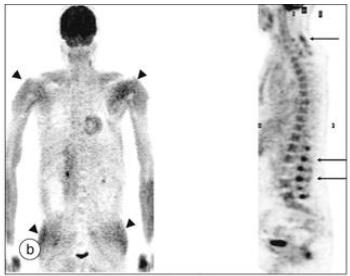

在可预见的未来,PET、MRI检查技术会引入到风湿疾病的分类标准之中。

PMR病人的PET显象:蓄积高的提示炎症活动